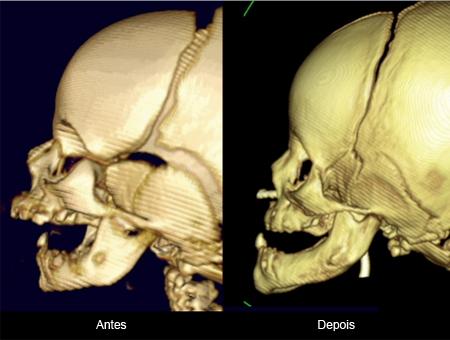

Neonatos com sequência de Pierre Robin (tríade de fenda palatina, microgenia e glossoptose) podem ter obstrução das vias aéreas superiores. É inicialmente tratada de forma não invasiva na posição pronada, trompete nasofaríngeo e/ou pressão positiva contínua nas vias aéreas (CPAP).[44] No entanto, até 23% dos recém-nascidos com micrognatia têm uma obstrução relacionada à língua e requerem intervenção invasiva com intubação endotraqueal caso posição prona, trompete nasofaríngeo e CPAP nasal não sejam eficazes.[45] O tratamento cirúrgico da obstrução das vias aéreas na micrognatia inclui adesão do lábio à língua, distração osteogênica mandibular (para mover a base da língua para frente e abrir as vias aéreas) e traqueostomia, que só deve ser realizada após todas as outras opções terem sido esgotadas.[44]

Um otorrinolaringologista pediátrico pode realizar uma avaliação das vias aéreas com laringoscopia flexível dinâmica para descartar outras anomalias das vias aéreas e tratar o refluxo laringofaríngeo associado.[Figure caption and citation for the preceding image starts]: Tomografia computadorizada (TC) de distração osteogênicaDo acervo de Travis T. Tollefson, MD, FACS [Citation ends].